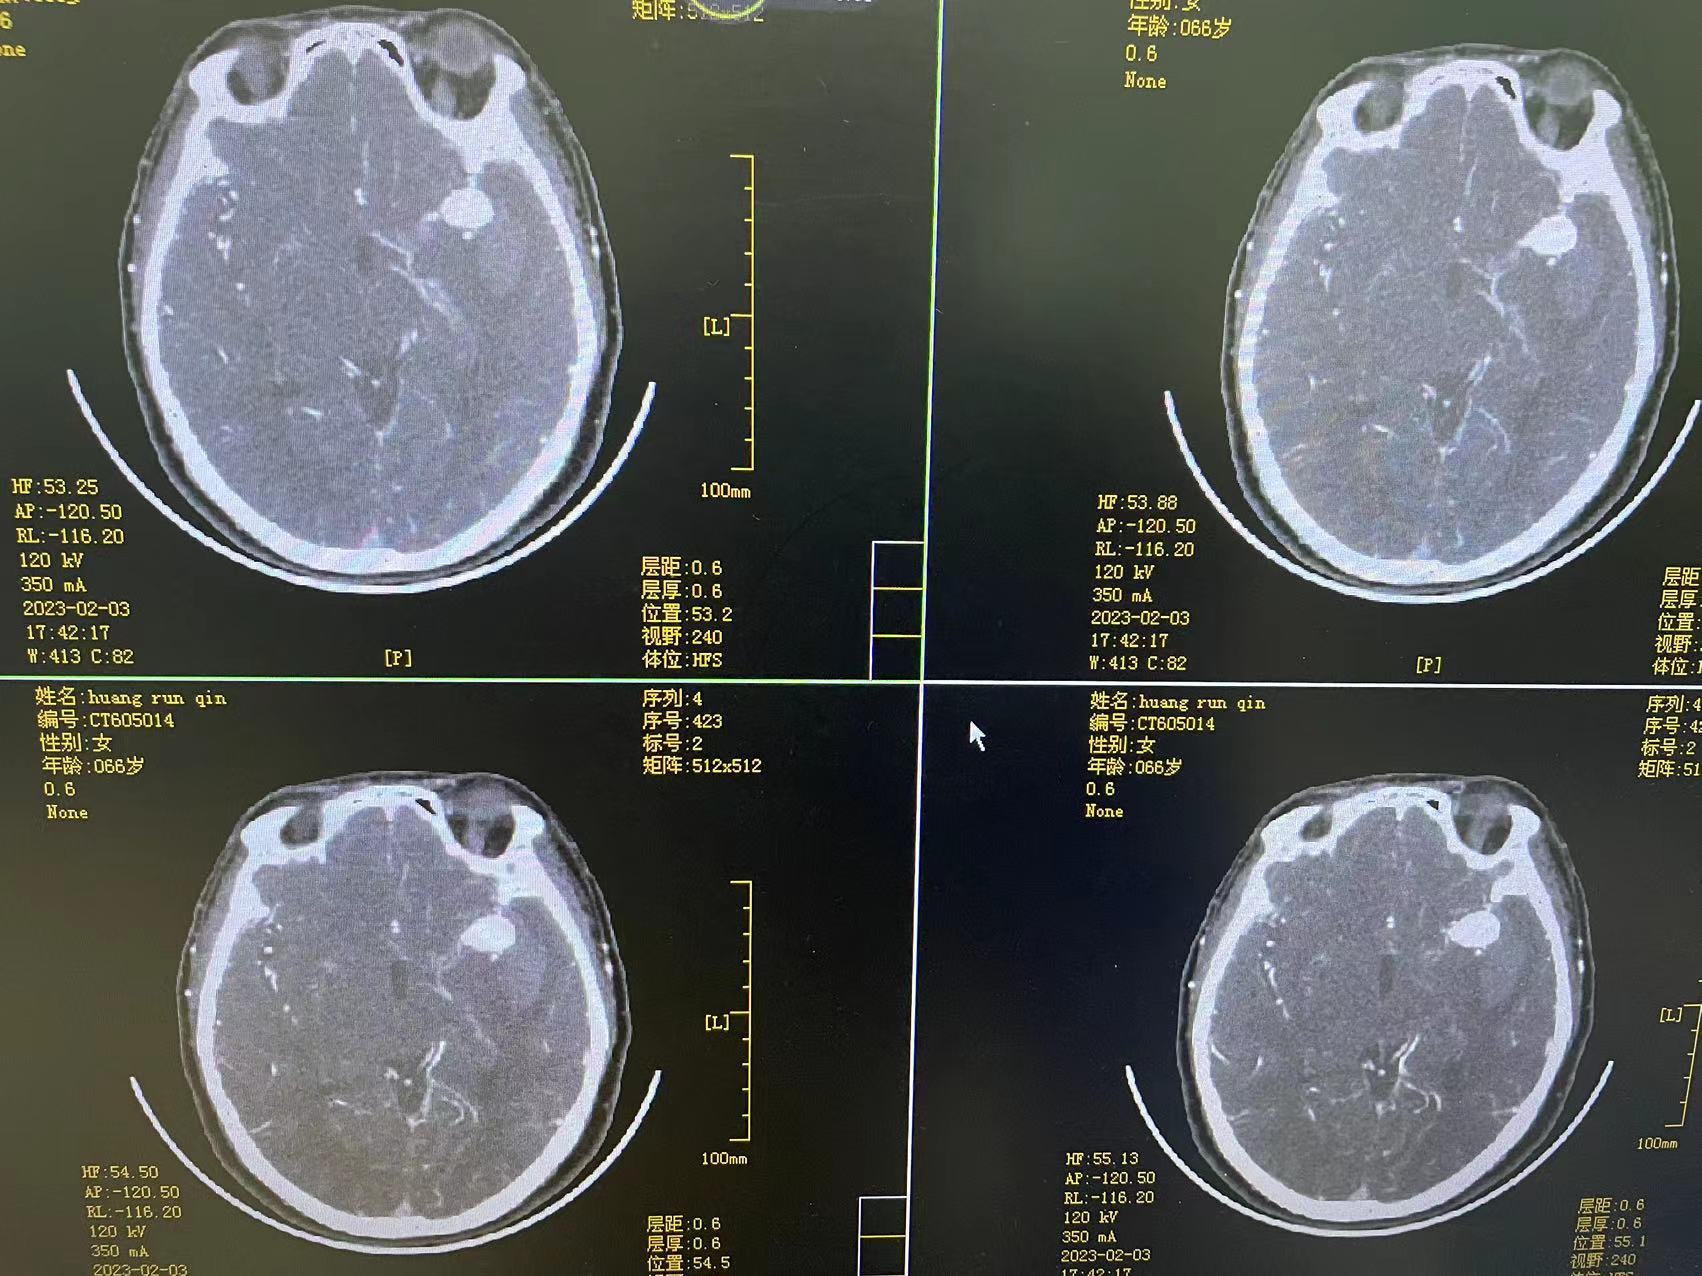

术后第十一天

术后第一个月

夹闭术后两个月,出院后一个月!再次出血,血肿量大,患者清醒!转上级市级医院,拟予介入栓塞后清除血肿